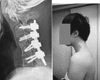

20.05.2025 02:44 МирФан Мужчине пришлось делать сложнейшую операцию на позвоночнике из-за использования смартфона: что произошло